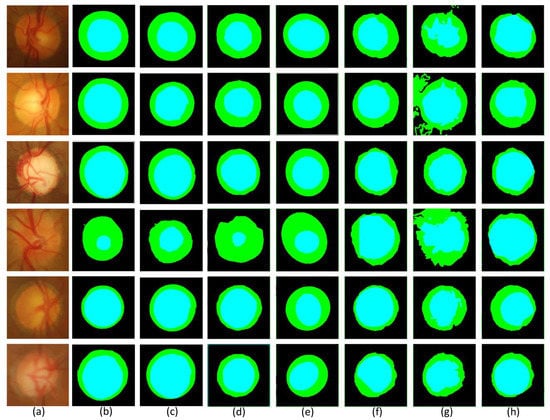

In the Drishti-GS1 dataset, this paper also provides an experimental comparison of MSMB-Net with other methods.

Figure 10 shows the results of the visualization comparison of MSMB-Net with other methods for the same image. The blue part of the figure represents the optic cup and the green part represents the optic disc. By comparing the blue part and the green part with the ground truth in the figure, we can find significant differences in the visualization of the optic disc and optic cup by different network models, especially in the segmentation of the edges of the optic disc and optic cup and the accuracy of the segmentation. The experimental results show that MSMB-Net is more accurate for the boundary segmentation of the optic disc cup. The result of BCRF segmentation of the optic disc is not ideal. The boundaries segmented by the Superpixel method are all regular ellipses, while the segmentation results of the optic disc cup using the Multiview, Graph Cut prior and Vessel bend methods are inaccurate and the boundaries are chaotic. For the method in this paper, the MBCM module is used to realize the feature extraction of objects of different sizes, which makes the boundary segmentation more accurate.

Figure 10.

Compares the segmentation results in the Drishti-GS1 dataset. (a) Original retinal image (b) ground truth (c) MSMB-Net (d) BCRF [50] (e) Superpixel [53] (f) Multiview [52] (g) Graph Cut prior [54] (h) Vessel bend [51].